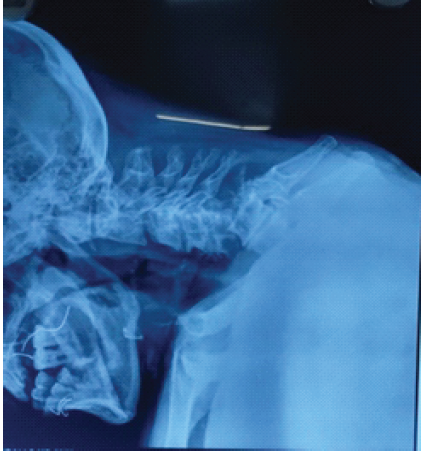

Sensory examination showed reduced sensation over the upper-limb dermatomes (C5–T1), whereas all sensations were preserved in the lower-limb dermatomes (L2–S1). Sacral sensory sparing was present, and the bulbocavernosus reflex was intact, confirming an incomplete injury. Deep tendon reflexes and muscle tone were normal. The patient was classified as ASIA impairment scale grade D, consistent with CCS. The patient presented with quadriparesis, with upper limb weakness more pronounced than lower limbs and reduced motor power and sensation in the upper limbs (Left > Right). The findings are suggestive of CCS. A plain radiograph of the cervical spine showed C5–C6 fracture dislocation (Fig. 2).

Figure 2: Cervical spine X-ray showing C5–C6 fracture dislocation